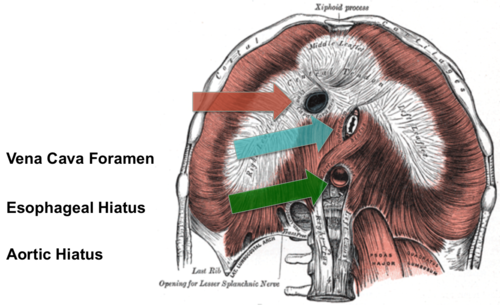

Diaphragma

Inandning

Foramen venae cava

röd pil

Hiatus aorticus

grön pil

Hiatus esophagus

blå pil